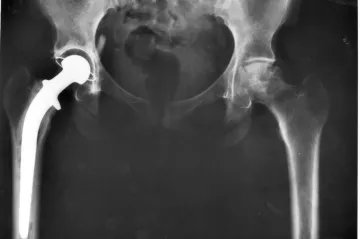

Endoprotézy se v Česku transplantují půl století. Nové technologie slibují i náhradu kmenovými buňkami

Před padesáti lety, v únoru 1969, v Československu proběhla implantace první totální endoprotézy kyčelního kloubu. Na I. ortopedické klinice v Praze ji provedl profesor Oldřich Čech, který se rovněž zásadním způsobem zasloužil o vývoj vlastní endoprotézy a rychlé rozšíření této léčebné metody v celé republice. A zatímco původně se pro operaci používal nerez, v současnosti jde o hlavičky z kobalt-chromu a v budoucnu by je dokonce mohly vystřídat náhrady vyrobené z kmenových buněk.

27. 2. 2019|